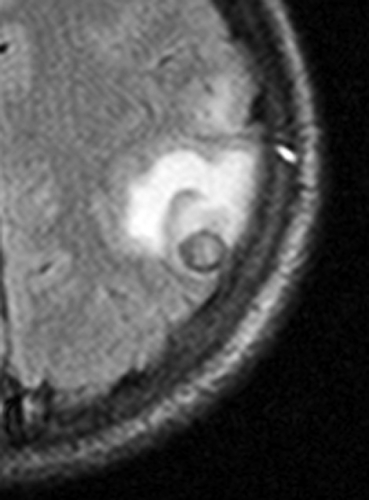

Datortomografi (DT) och magnetresonanstomografi (MRT) påvisade en solitär, drygt 1 cm stor rundad lesion i övergången mellan vit substans och kortex parietalt i vänster hjärnhalva. Förändringen var omgiven av en kontrastuppladdande kapsel och av ett ödem, som sträckte sig över hela den främre delen av vänster hemisfär (Figur 1 och Figur 2).

Differentialdiagnosen ur neuroradiologisk synvinkel omfattade bakteriell hjärnabscess och parasitinfektion, främst neurocysticerkos, men neoplasi (hjärntumör eller tumörmetastas) kunde inte med säkerhet uteslutas. Bilderna förmedlades via patientens familj till flera neurokirurger i patientens hemland, som samstämmigt ansåg att neurocysticerkos var mest sannolikt. I cerebrospinalvätska var antalet av polynukleära leukocyter diskret förhöjt (2,5 106/l). Western blot-analys av serum och cerebrospinalvätska påvisade inga antikroppar mot Taenia solium. Serologi för Toxoplasma gondii var negativ. I fecesdirektmikroskopi och i tejpprov fann man inga maskägg. Normalt ögonfynd konstaterades vid ögonläkarundersökning. Ett elektroencefalogram visade diffus förlångsamning med vänstersidig övervikt.

Nästa steg är en DT- eller hellre en MRT-undersökning av hjärnan. Fynden i DT kan vara relativt ospecifika medan MRT ger bättre information om cystans innehåll. Vid neurocysticerkos ser man en eller flera cystor med kontrastladdande rand. Ibland kan parasitens skolex identifieras som en millimeterstor punkt, vilket gäller som ett säkert diagnostiskt tecken [6]. Äldre cystor förkalkas. Om den radiologiska undersökningen visar en patologi förenlig med neurocysticerkos analyseras serum eller cerebrospinalvätska med antikroppstest (immunblot-teknik enligt Tsang [7]). I Sverige utförs testet inte rutinmässigt, men prov kan lämnas till Smittskyddsinstitutet, som vidarebefordrar det till Schweiz. Testets specificitet anges till 100 procent, medan sensitiviteten varierar: upp till 95 procent vid multipla, icke-förkalkade intracerebrala lesioner och enbart ca 50–80 procent vid solitära cystor. Testet kan inte skilja mellan aktuell och genomgången infektion. Eosinofili i cerebrospinalvätska (men inte i blod) kan tyda på neurocysticerkos; differentialräkning av celler i cerebrospinalvätska kan genomföras manuellt i ett färskt likvorprov.

Anamnesen och den radiologiska bilden gjorde att den kliniska misstanken om neurocysticerkos var relativt stark. Däremot var de radiologiska förändringarna inte entydiga, någon skolex kunde inte identifieras. Dessutom var serologin negativ, och i likvor fanns en lätt pleocytos.